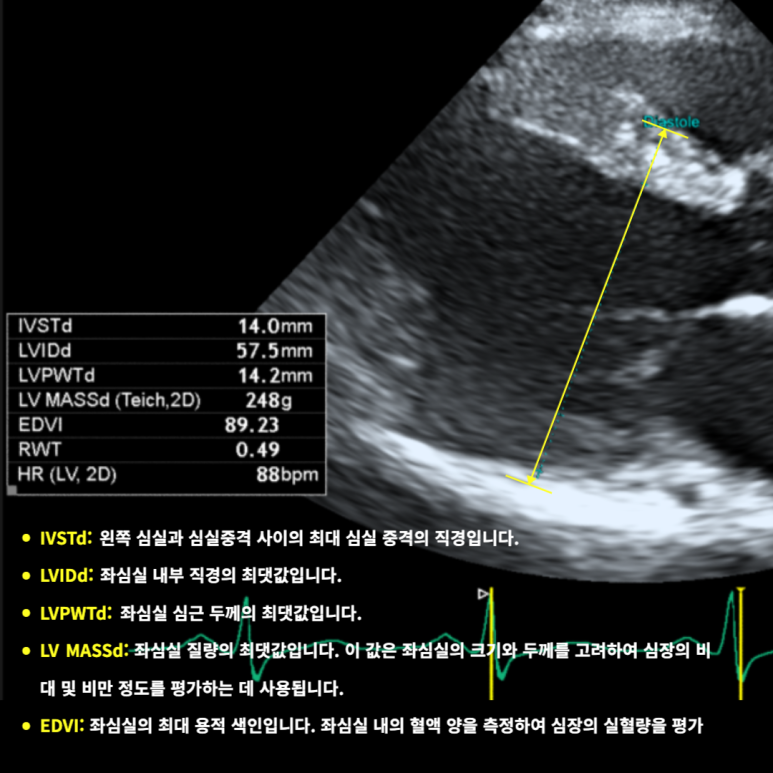

좌심실비대(LVSTd 14mm↑), 좌심실내경 LVIDd 57.5mm(경계), 대동맥판 역류심장수축기능(EF 20–30%) 저하 확인. 심부전으로 판단해 상급병원 입원치료를 의뢰했습니다.

• 심초음파: 좌심실비대/확장 심초음파: 좌심실비대/확장